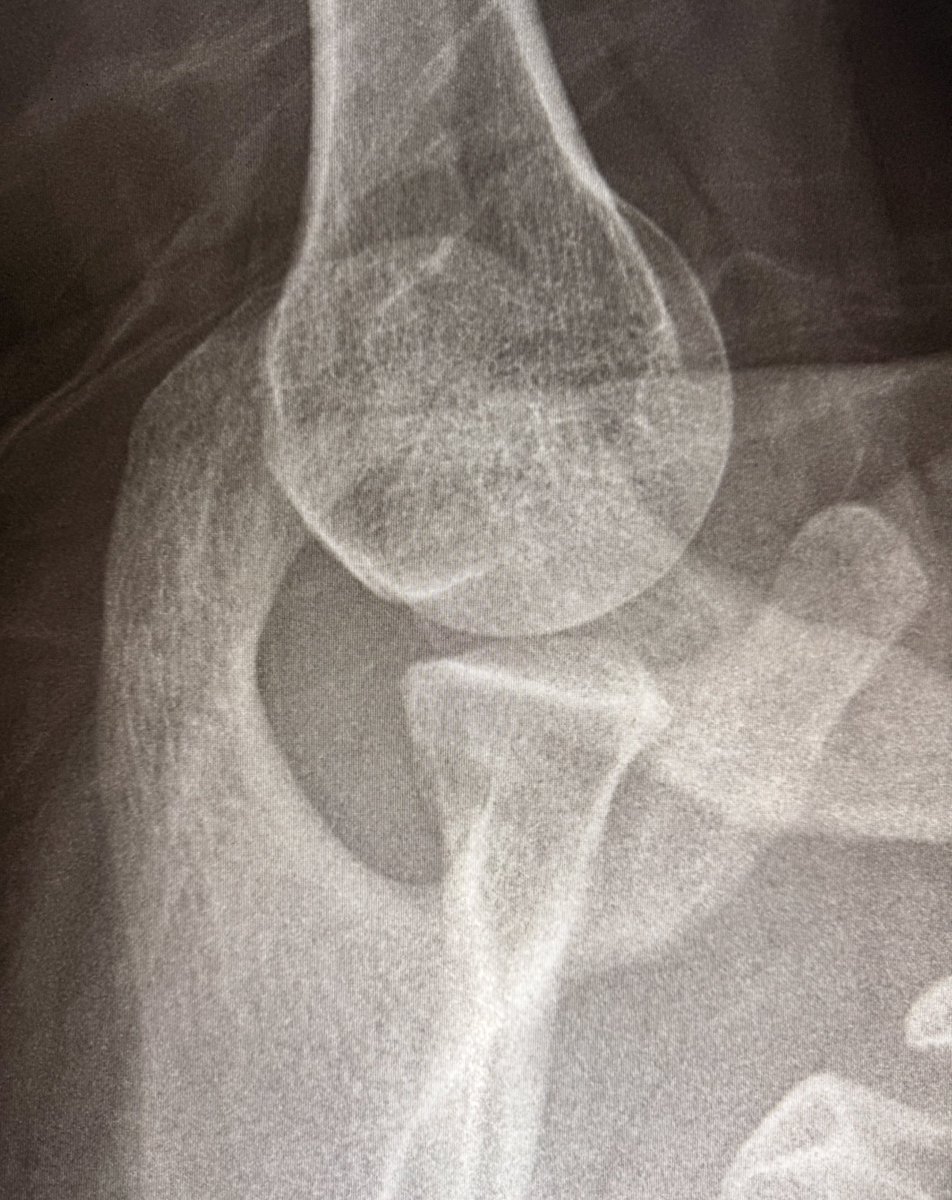

Tell me which is your favorite radiographic projection and why it is axillary view of the shoulder? 😅 Majestic! I have a soul crush on this view!

Tell me which is your favorite radiographic projection and why it is axillary view of the shoulder? 😅

Majestic! I have a soul crush on this view!